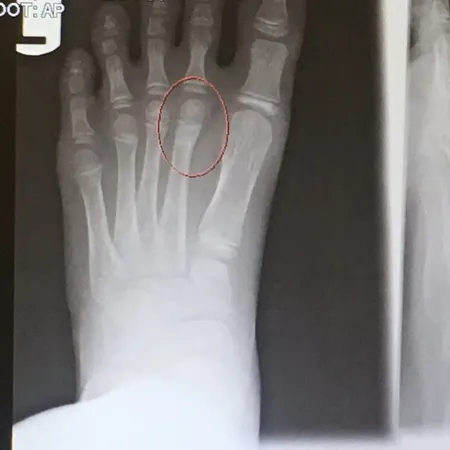

Pediatric Metatarsal Neck Fractures

Below is an x-ray image of an extra-articular fracture of the proximal phalanx of the hallux (great toe) of a child. the fracture line does not enter the joint.